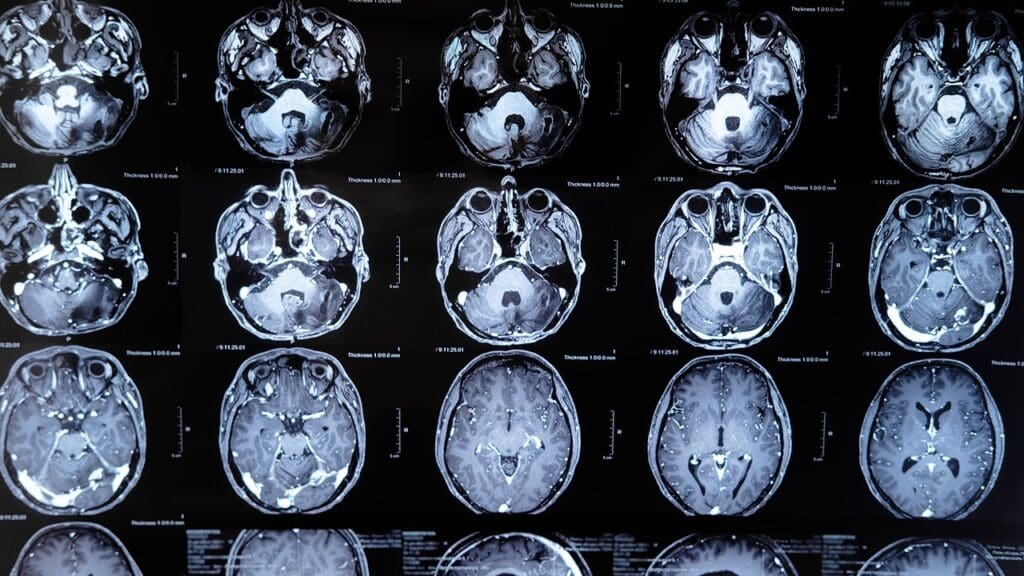

To diagnose cerebral edema, we use a mix of advanced imaging and clinical checks. We have many tools to spot and treat cerebral edema accurately.

CT scans are key for finding cerebral edema, mainly in emergencies. Each type of edema shows up differently on CT scans. For example, vasogenic edema looks like a dark area with lines going into the white matter.

MRI gives us detailed info on cerebral edema. It uses special techniques like diffusion-weighted imaging (DWI) and apparent diffusion coefficient (ADC) mapping. MRI is great for seeing how edema changes and if treatments are working.

Doctors use imaging studies like CT and MRI scans to diagnose cerebral edema. They also do clinical evaluations and monitor brain pressure. This helps them understand the severity and type of edema.